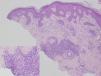

Se hizo una biopsia cutánea para estudio histológico (fig. 3), que puso de manifiesto una epidermis hiperplásica con hiperqueratosis, hipergranulosis focal, acantosis y papilomatosis. En la dermis se observaba un infiltrado inflamatorio crónico con granulomas sin necrosis caseosa, formados por células gigantes multinucleadas tipo Langhans y una corona de linfocitos. La tinción con PAS fue negativa para hongos y con la técnica de Ziehl-Nielsen no se vieron bacilos resistentes al ácido y al alcohol. Con luz polarizada no se visualizó material birrefringente.